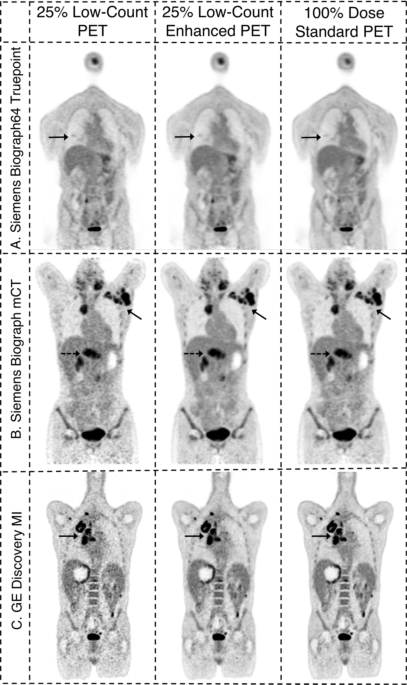

An example image of subjects scanned on three different PET scanners with body mass index (BMI) of over 30 is shown below. Traditionally, PET scans are sensitive to varying body habitus and suffer from low signal-to-noise ratio in subjects with higher BMI. We demonstrate how our method improves the diagnostic image quality of low-count PET scans even in high BMI patients.